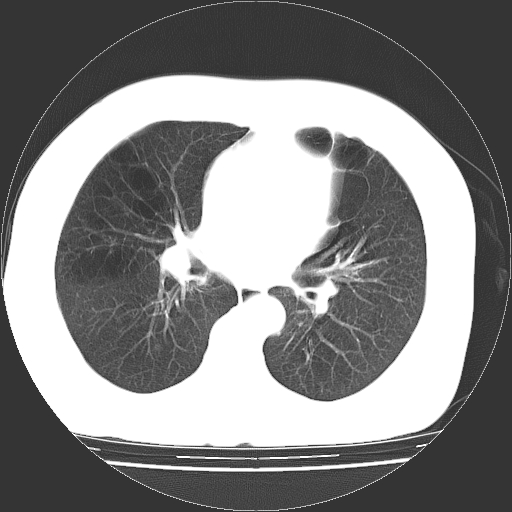

标题: CT13141:女,70岁,咳嗽、胸闷半个月。 [打印本页]

标题: CT13141:女,70岁,咳嗽、胸闷半个月。

女,70岁,咳嗽、胸闷半个月。纵隔窗未见异常,未上传。

慢支炎、肺气肿征,双肺多发肺大泡

小叶中心型肺气肿并多个肺大泡形成。

小叶中心性肺气肿及间隔旁肺气肿.(多与吸烟有关)